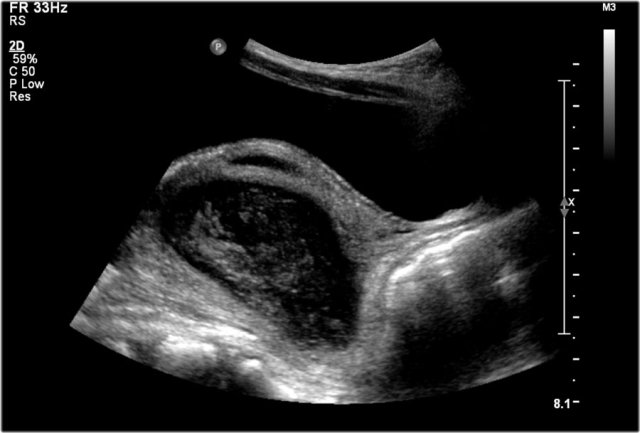

The US- image shows a cystic lesion in the lower abdomen in a 3-year-old girl with colicky abdominal pain.

At operation a torsion of the right adnex was seen.

On pathology a teratoma was demonstrated.